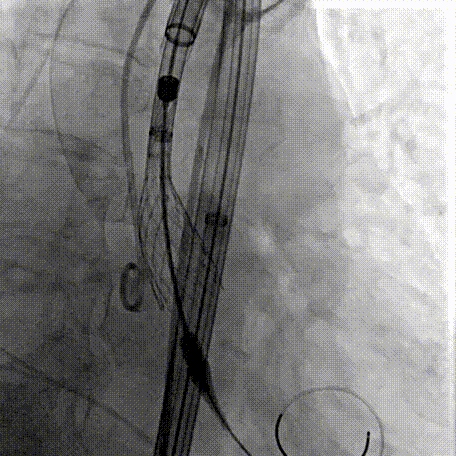

Step 2.建立大鞘通路:大鞘通过升主、边进入边加弯,避免剐蹭弓部斑块

Step 4.输送系统进入:过弓性能优异,悬空通过,整体过程未将鞘管顶起至弓顶部